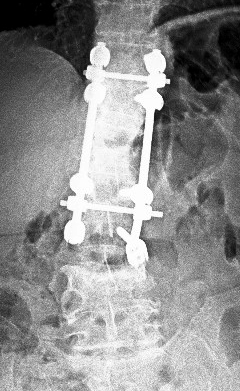

Direkt

grafilerde L4 vertebrasındaki kırık yanında, eski bir L1 kırığı

nedeniyle yerleştirilmiş olan T11-L3 transpediküler vida sisteminin

disfonksiyone olduğu görülüyor. L3 vidasında sağ tarafta muhtemelen

gevşemeye bağlı vida çıkması, solda ise vida başının roddan kurtulduğu

görülüyor.